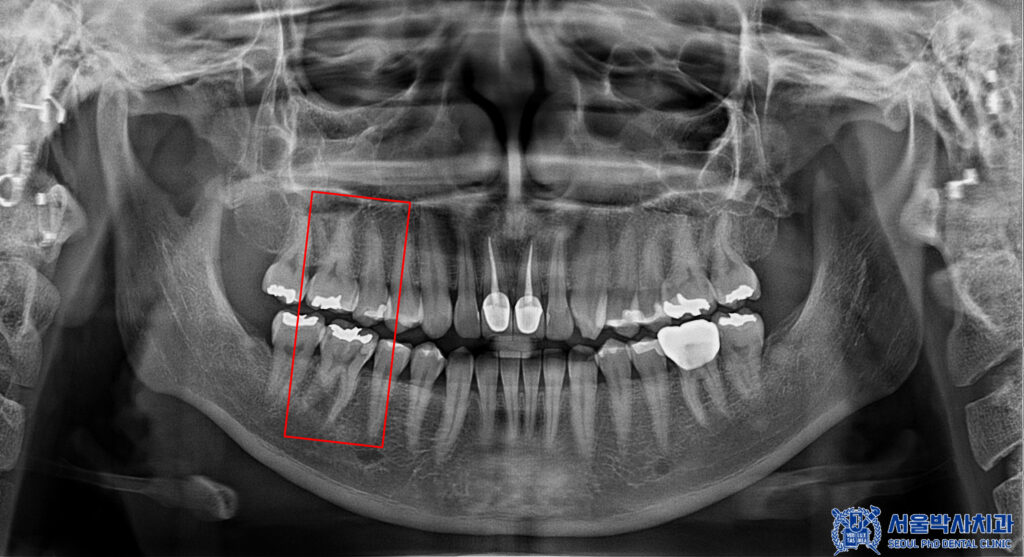

확인 결과,

오른쪽 위·아래 치아에

충치가 진행되어 있었고,

이로 인해 치주염과 치수염까지

동반된 상태였습니다.

또한 정밀한 확인을 위해

3D CT를 촬영하였습니다.

위쪽 치아 뿌리 끝 염증을

확인할 수 있었습니다.